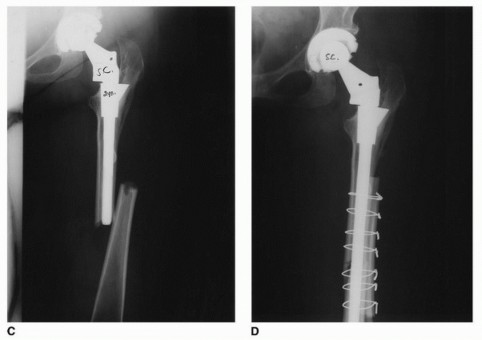

General THA Complications in Complex Anatomy

- Intraoperative Periprosthetic Fracture: The preparation of deformed, sclerotic, or osteoporotic bone carries a high risk of fracture. Prophylactic cable placement around the proximal femur prior to broaching is often recommended in high-risk cases.

- Subsidence: Failure to achieve adequate distal cortical engagement can lead to axial subsidence of the stem.

| Intraoperative Calcar Fracture | 3 - 8% | Cerclage wiring or cabling; bypass fracture by 2 cortical diameters with the distal stem. |

| MACC / Pseudotumor (ALTR) | 1 - 5% (Design dependent) | Revision THA with debridement of necrotic tissue; conversion to monolithic stem if anatomy allows, or use of ceramic heads with titanium sleeves. |

| Modular Junction Dissociation | < 1% | Immediate open reduction, meticulous cleaning of tapers, and re-impaction. If tapers are damaged, component revision is required. |

| Stem Fatigue Fracture | < 1% | Extraction of distal segment (often requires extended trochanteric osteotomy or trephine reamers); revision to a larger diameter, robust modular or monolithic revision stem. |